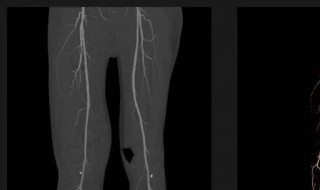

你好,冠状动脉有钙化点常表示冠状动脉硬化,根据钙化的程度不同,临床表现也不同,轻者可以无症状,严重者可以引起心绞痛,甚至心肌梗塞等。另外患者还有高血脂,这是引起冠心病的一个易患因素。

5、必要时行冠状动脉造影后行介入治疗。